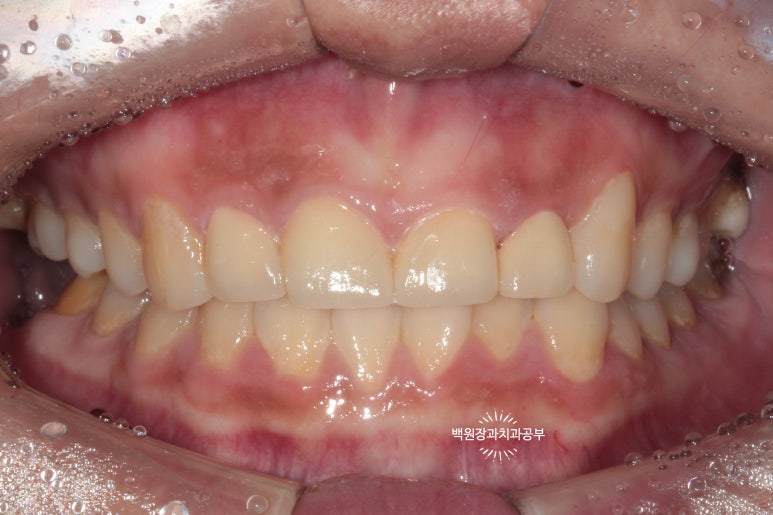

지르코니아 크라운 및 잇몸치료 전후비교 들어갑니다.!!

앞니 지르코니아 치료 전보다 치료 후가 상당히 이상적인 모습을 띄고 있는데요,

성공적인 앞니 지르코니아 크라운 치료 후 다음과 같은 장점을 얻을 수 있었습니다.

앞니 충치치료의 완료

앞니 사이 공간의 폐쇄와 가지런해짐

앞니 색상의 개선

보다 작아진 치아크기로 얻어진 조화로움

잇몸치료 후 개선된 잇몸 건강 (건강한 coral pink color의 색상과 부종의 사라짐)

위 네가지의 개선사항은 아마 쉽게 확인하실 수 있으실거에요!

잇몸이 건강해지는 것은 은근히 인지하기 어려운데요, (아마 우리가 치아를 보는데 익숙해서일거에요.) 치주과를 전공한 제게는 잇몸이 건강해짐이 가장 먼저 보이더라구요. ㅎㅎㅎㅎ

위에 표시해둔 파란색 타원 내부를 보시면, 무엇보다 색상의 개선이 명확하고 (이를 치과의사들은 coral pink라고 부릅니다.) 염증이 사라지고 붓기가 개선되어 날카로운 모양을 되찾게 되었습니다.!!!

잇몸치료 후 이제는 더 이상 양치날 때 피가 나지 않는다고 하셨어요.! 이래서 잇몸치료가 정~말 중요합니다.